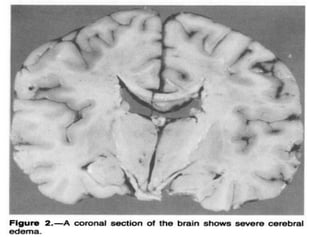

Disequilibrium Syndrome

Def: Cerebral edema resulting from urea removal from the

blood more rapidly than from the CSF and brain tissue

generating a urea osmotic gradient responsible for water

moving into brain cells.

Disequilibrium Syndrome Def: Cerebraledema resulting from urea removal from the blood more rapidly than from the CSF and brain tissue generating a urea osmotic gradient responsible for water moving into brain cells.